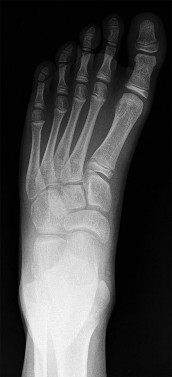

A 13-year-old girl sustains an ankle injury during a soccer match. Radiographs reveal an isolated Salter-Harris III fracture of the anterolateral distal tibial epiphysis (Tillaux fracture). Which of the following describes the anatomical sequence of distal tibial physeal closure that predisposes adolescents to this specific fracture pattern?

A 13-year-old female sustains a fracture of the anterolateral aspect of her distal tibial epiphysis after an external rotation injury. This fracture pattern (Tillaux fracture) occurs specifically due to the asymmetrical closure of the distal tibial physis. In what sequence does the normal distal tibial physis close?

A 13-year-old girl sustains an ankle injury during a soccer game. Radiographs reveal a Salter-Harris type III fracture of the anterolateral aspect of the distal tibial epiphysis (Tillaux fracture). This fracture pattern is primarily caused by an avulsion of which of the following structures?